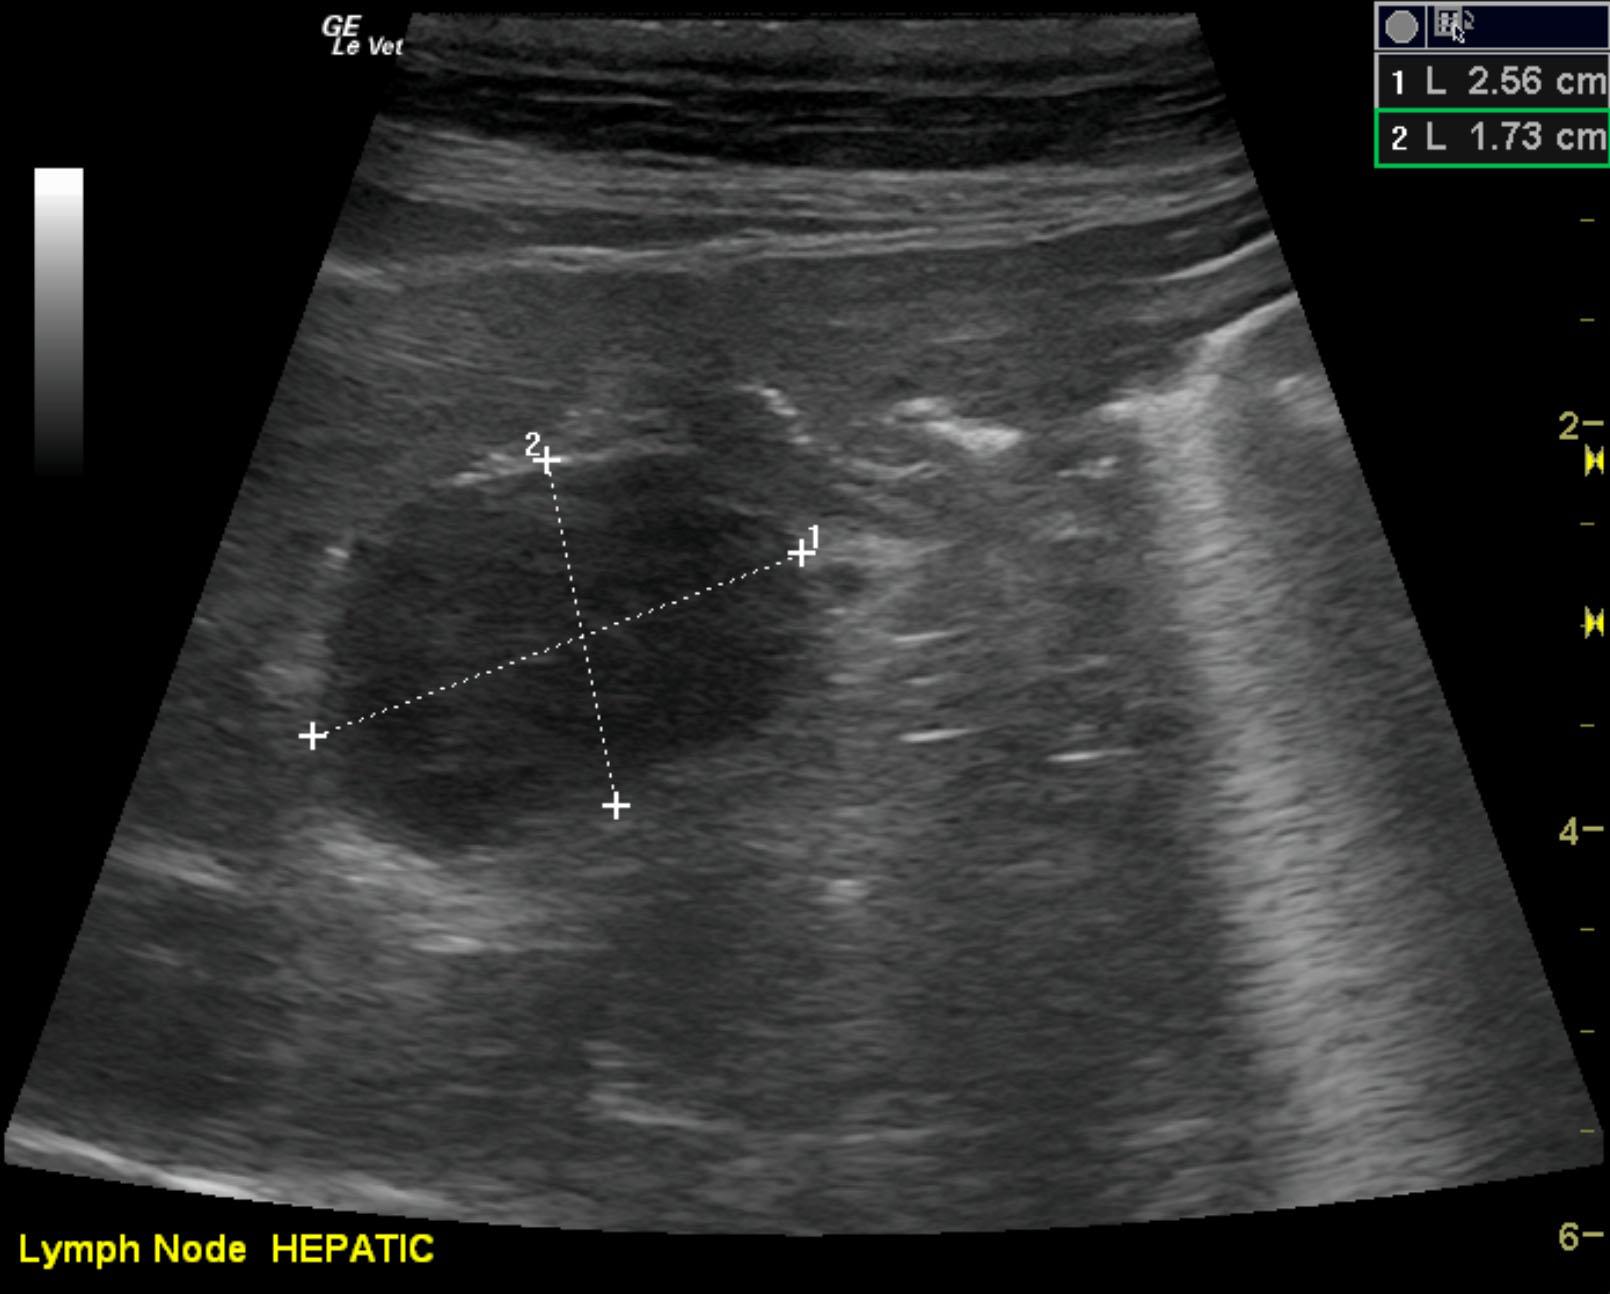

The patient is a feline DSH, NM, 14 years. The patient was hospitalized last week for pancreatitis, but specfPL remains elevated and has increased. The patient is now anemic and albumin is 2.2.